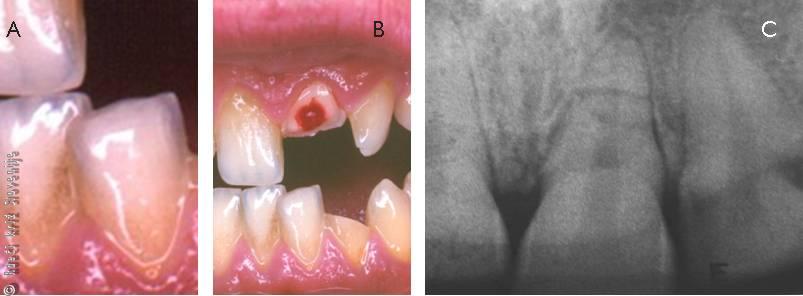

Slika 6

A – Izbitje zob - s krvnim strdkom izpolnjeni zobnici.

B – Pravilno ponovno vsajena izbita zoba, ki sta začasno imobilizirana z rahlim ugrizom preko gaze.

C – Izbita zoba shranjena v fiziološki raztopini. Drobnih nečistoč na površini pred ponovno vstavitvijo ne strgamo.

D – Končna imobilizacija ponovno vsajenih zob je

elastična in traja 7 do 14 dni, v primeru pridruženega zloma zobnice 4 do 6 tednov.

12-letna deklica je padla z rolerji in se udarila na zobe. 5 minut po poškodbi je prišla domov v spremstvu dveh sošolk, ki sta povedali, da sta na tleh videli izbit zob. Starši so odšli na kraj padca in res našli izbite zobe, ki so jih zavili v suh in čist robec. Do najbližjega zdravstvenega doma so potrebovali 20 minut. Tam je deklico pregledal splošni zdravnik, ki je ugotovil, da ima ranico na zgornji ustnici in na dlesni ter prazne zobnice v predelu zgornjih sekalcev (Slika 9). Poškodovanih zob si ni ogledal, ampak je deklico nemudoma poslal do zobozdravnika v sosednji stavbi, ki pa tega dne popoldan ni delal. Po nasvetu medicinske sestre so se poškodovanka in njeni starši odpravili v bolnišnico, kamor so prispeli dve uri po poškodbi.

Slika 9

Prazne in delno poškodovane zobnice v področju zgornjih sekalcev.